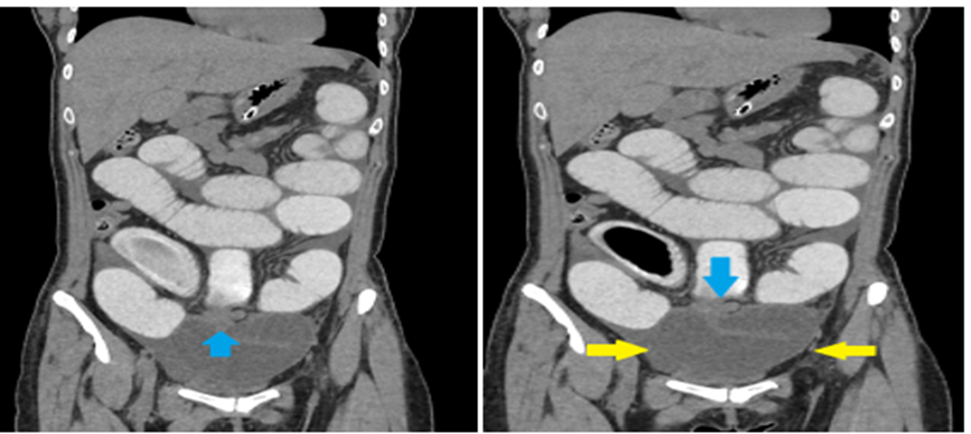

Multidetector computed tomography (MDCT) of the abdomen with oral non-ionic contrast demonstrated a tubular structure arising from the distal ileum, showing two adjacent transition points (the “double-beak” sign), a C-shaped closed-loop configuration, and convergence of mesenteric vessels toward the diverticular base. These findings were consistent with a closed-loop small bowel obstruction (SBO) secondary to Meckel’s diverticulum. [Figure 2] [Figure 3] [Figure 4]

Figure 4: Left image: Coronal contrast-enhanced CT image of the abdomen demonstrating a Meckel’s diverticulum forming a ring-like fibrous band around a segment of distal small bowel (blue arrow), consistent with internal herniation. Proximal to the transition, there are contrast-filled, dilated small bowel loops, while a collapsed, C-shaped, fluid-filled obstructed loop is seen distal to the point of constriction—findings suggestive of closed-loop small bowel obstruction. Right image: Coronal CT image of the abdomen shows a C-shaped, fluid-filled loop of obstructed small bowel (yellow arrowheads), consistent with a closed-loop obstruction. A fibrous band arising from a Meckel’s diverticulum (blue arrow) is seen encircling the distal ileal loops, forming the transition point. Dilated, contrast-filled proximal small bowel loops are observed above the site of obstruction.